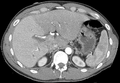

A CT scan in which the liver and portal vein are shown.